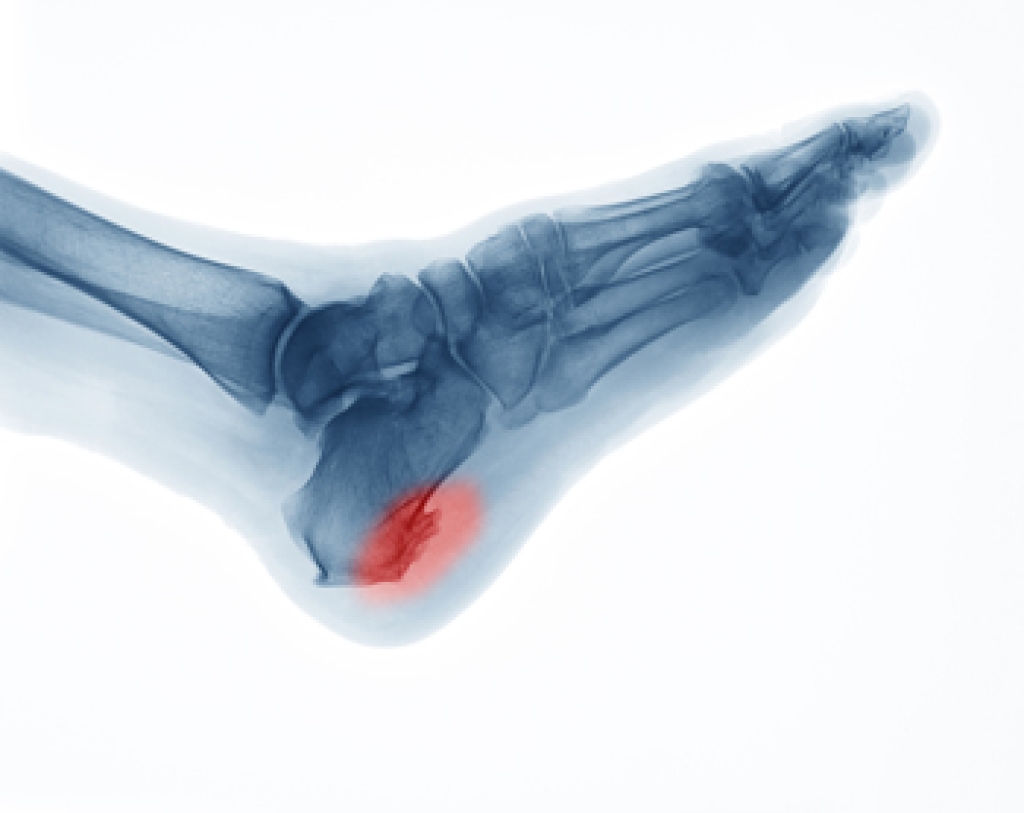

The feet contain 26 bones each, creating numerous joints and surfaces where bone spurs may develop from repeated stress, inflammation, or injury. These bony growths, known as osteophytes, often form when the body responds to pressure or friction. If conservative care does not ease symptoms, a podiatrist may suggest surgery to remove the bone spur or address any tight tissues that may be contributing to discomfort. Resection surgery trims away the excess bone, and the type depends on the location. A dorsal spur excision is on the top of the foot, an inferior heel spur resection is under the heel, and a posterior heel spur removal is at the back of the heel. If soft tissue is involved, plantar fascia release or partial Achilles tendon release may be employed. In cases of severe joint damage, joint fusion can stabilize the area while joint replacement can restore movement. If you are experiencing this type of foot pain, it is suggested that you schedule an appointment with a podiatrist for an exam and appropriate treatment options.